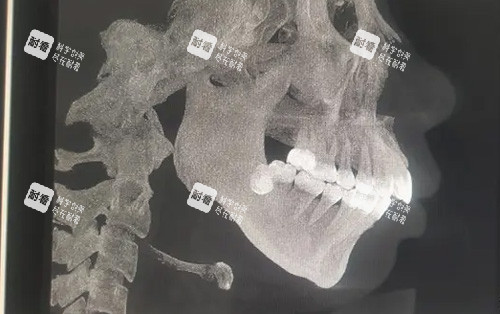

“我的方案要12万,因为除了凸嘴还有轻微偏颌。”林小姐翻着术前CT片,“艾医生用3D软件模拟了术后结果,连笑起来苹果肌的弧度都算好了。”这钱里藏着不少“隐形价值”:

3D智能化导板:把截骨线误差从传统手术的2毫米压缩到0.1毫米,相当于用游标卡尺搞雕刻